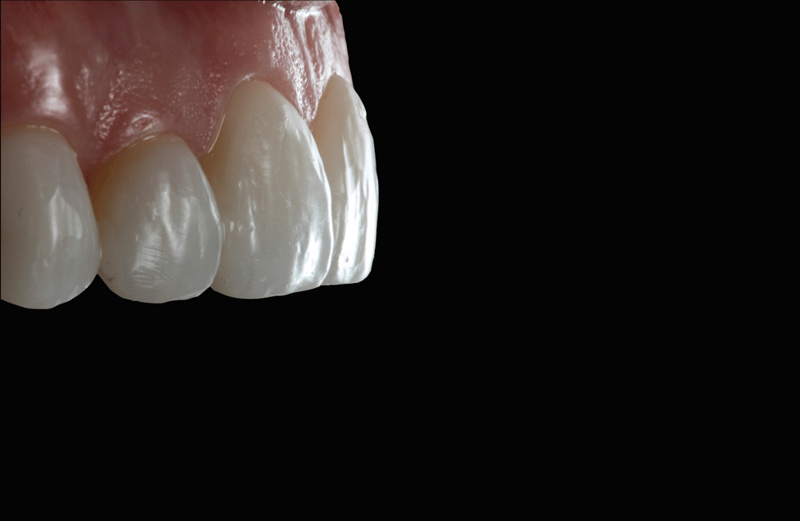

- Polishing and Preparation for Cementation: The veneers were contoured and polished using the Jiffy™ Natural polishing kit, readying them for the cementation process.

- Facial Anatomy: To develop the facial anatomy, football diamond and long, thin diamond burs were used. A lobed diamond bur was used to create the lines of Retzius (SR lines). The initial polishing was completed with Jiffy™ Natural polishers, then the final luster was achieved with Ultradent™ Diamond Polish Mint and the Jiffy™ Goat Hair Brush (not available in Europe) to not remove the tertiary anatomy.